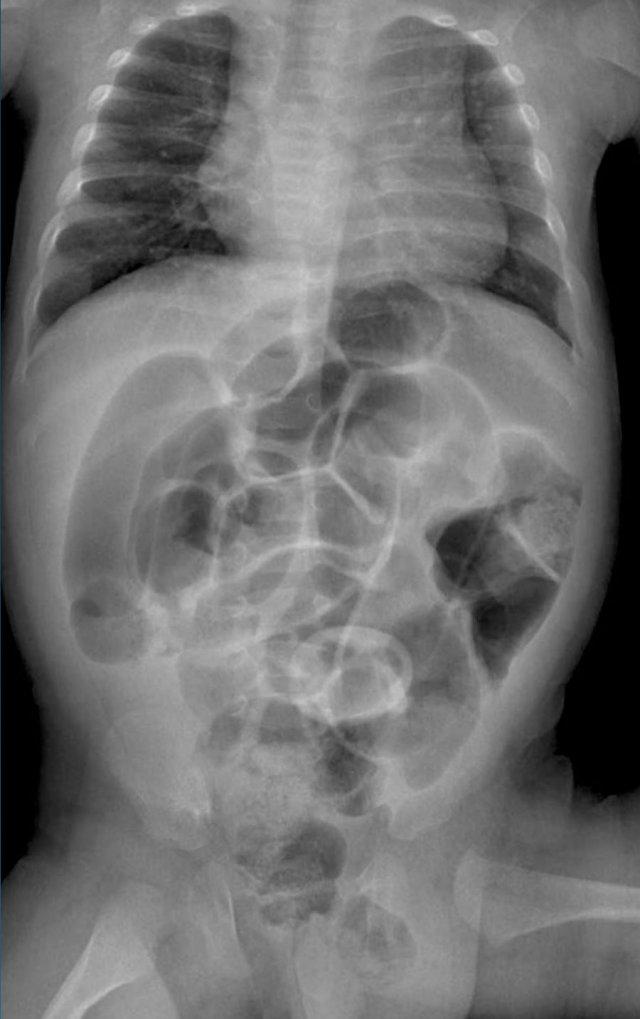

Đây là hình ảnh của một trẻ sơ sinh phát triển viêm ruột hoại tử.

Ở giai đoạn sớm này, X-quang chỉ cho thấy hình ảnh giãn ruột không đặc hiệu.

Ở giai đoạn này, không thể xác lập chẩn đoán.